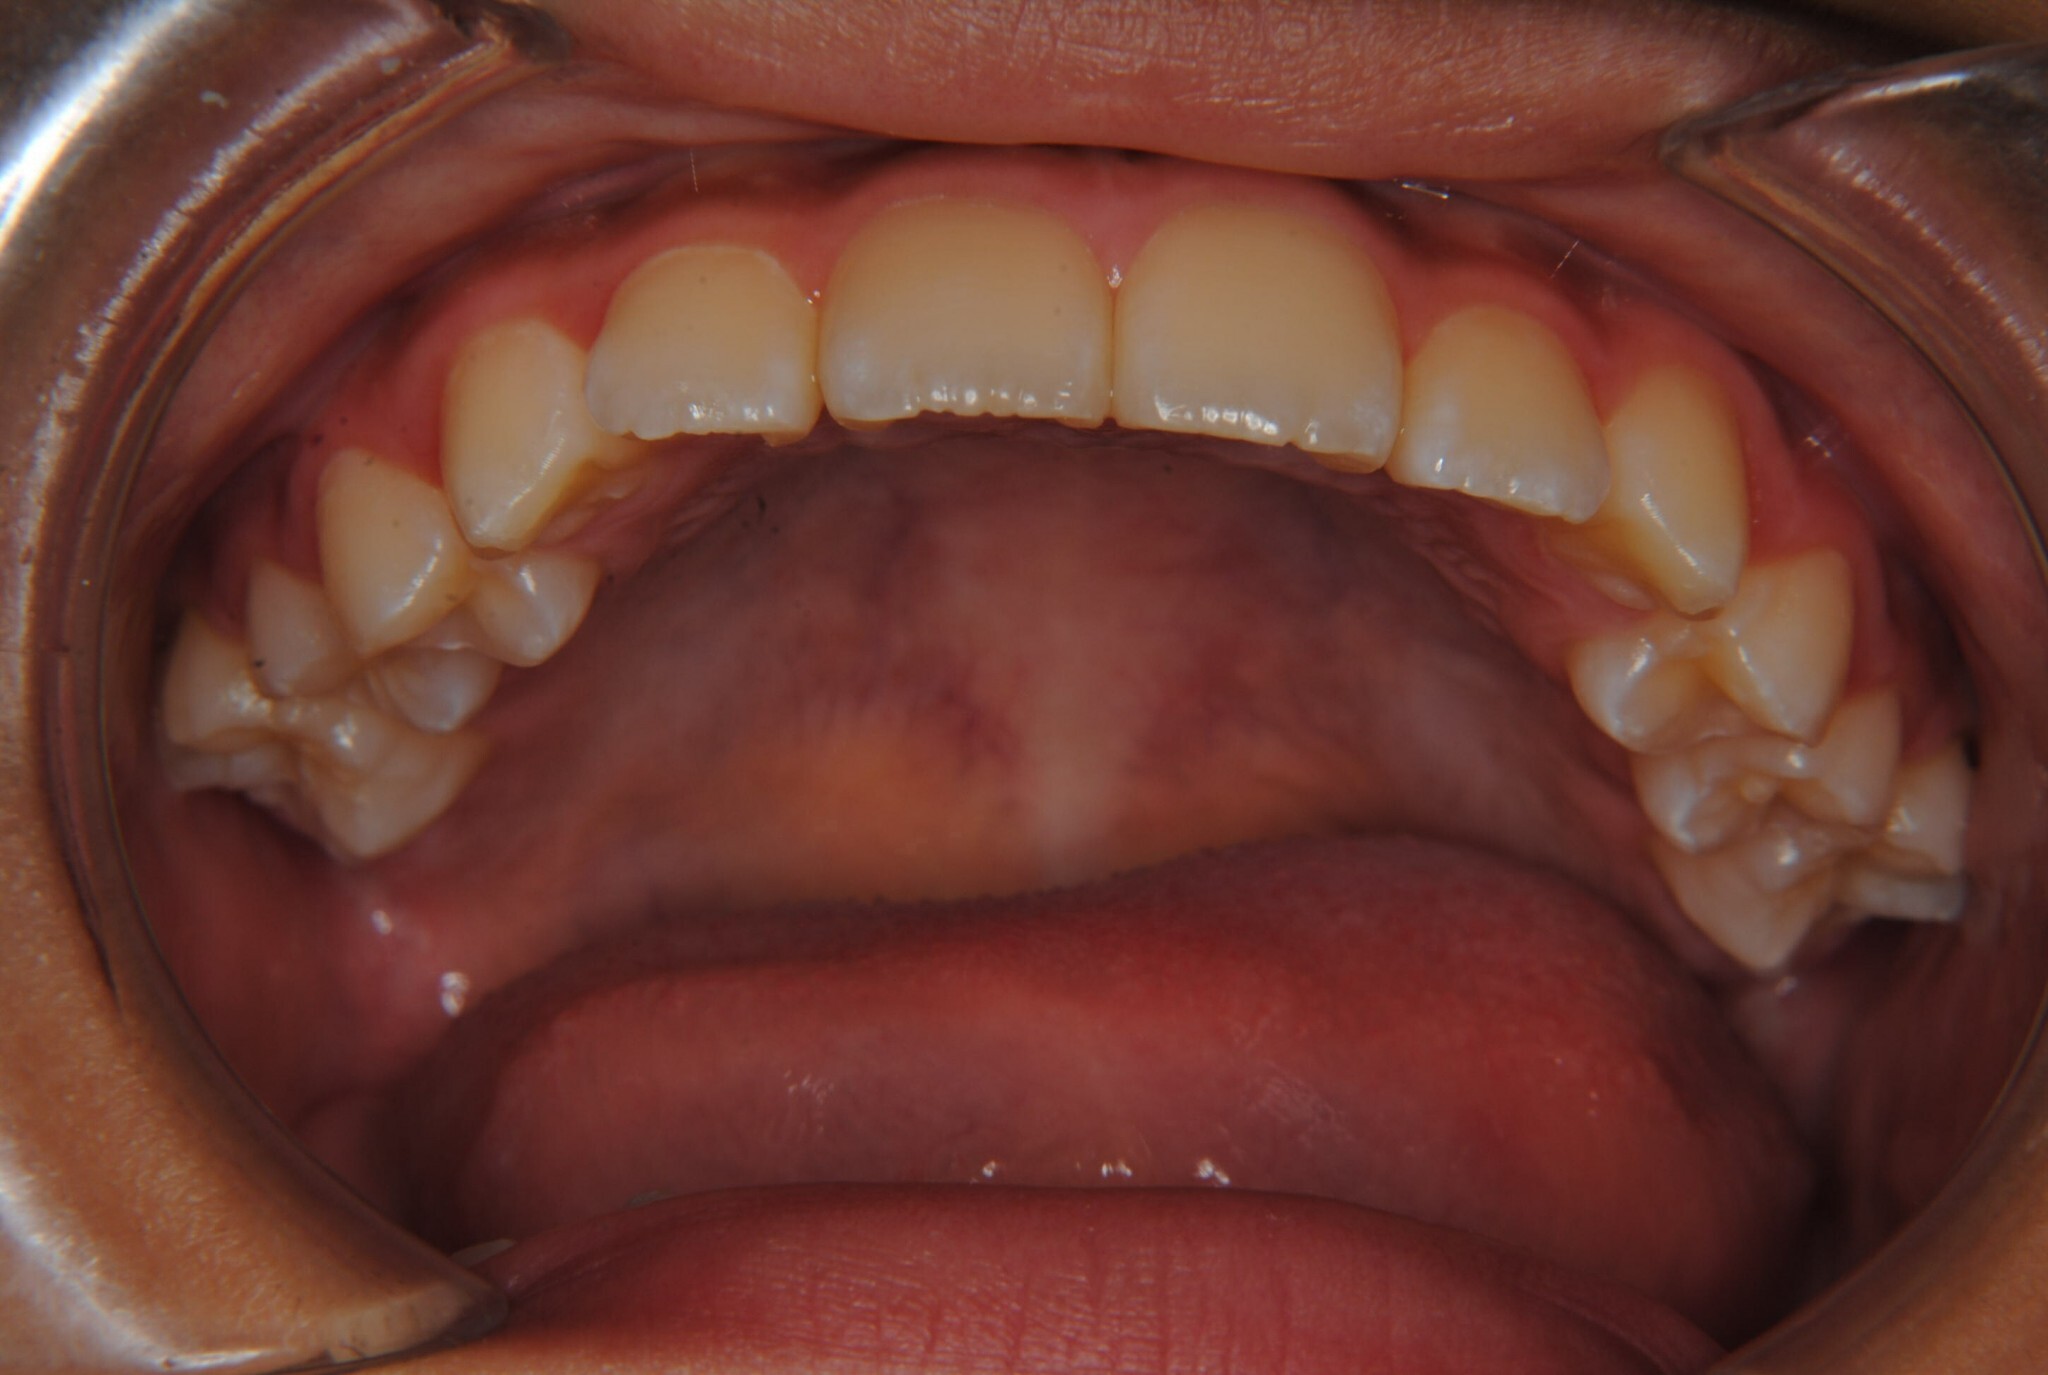

②診断名:Ⅰ級叢生

③年齢:初診時(左写真)8歳6か月、終了時(右写真)11歳4か月

④治療に用いた主な装置:拡大床

⑧リスクと副作用:特に大きなリスクや副作用はありませんでした。拡大床装着直後は違和感があったようですが、特に痛みを感じることなく6.5mmまで拡大できました。その後永久歯への生え変わりも順調で、ほぼ正常な咬み合わせになりました。この後11歳4か月まで観察し、7番目の奥歯である12歳臼歯がきちんと咬んだので終了となりました。